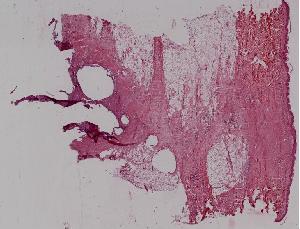

24. Granulomatous inflammation of the lung ( miliary tuberculosis of the lung)